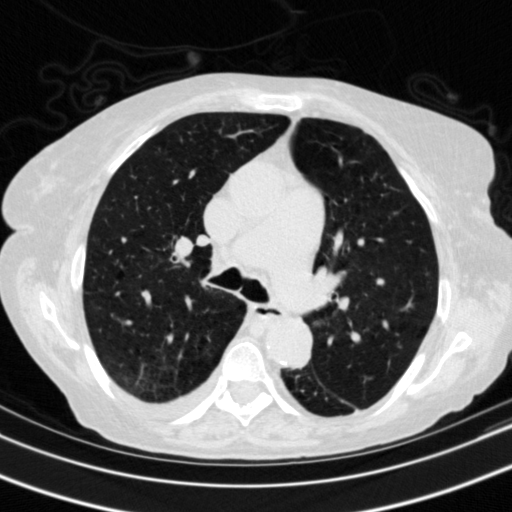

Targeted Slice 70 - Lung Window Analysis (Generated vs Real Venous)

0.598

Lung SSIM

162.3

Lung RMSE

72.3

Lung MAE

Average Lung Window Metrics Across All Slices (153 slices) - Generated vs Real Venous

0.579

Lung SSIM (Avg)

146.5

Lung RMSE (Avg)

66.3

Lung MAE (Avg)

Generated VENOUS CT scan (A→B translation)

Lung window (WL -600, WW 1500 β†’ Low βˆ’1350, High +150)

Actual HU range: [-1201.8, 150.0]